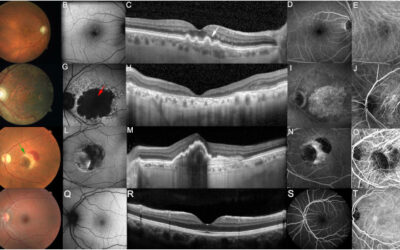

Se acelera la investigación en terapia génica para las enfermedades de la retina

Se acelera la investigación en terapia génica para las enfermedades de la retina Los investigadores se muestran optimistas ante la posibilidad de que la terapia génica pueda atender una amplia gama de enfermedades oculares, incluidas algunas que actualmente no tienen...